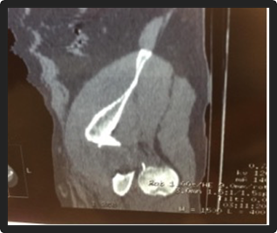

Presentamos el caso de un paciente de 49 años, trabajador de la construcción, sin patología previas, procedente del interior del Uruguay, quien otorgó su consentimiento verbal y escrito para la publicación de su caso. Sufre un accidente automovilístico en febrero del 2019, viajando como acompañante en asiento trasero sin cinturón de seguridad, sufriendo lesión de cadera izquierda al impactar la rodilla con el respaldo del asiento delantero. De la valoración inicial al momento de la asistencia en el lugar, no presenta lesión de cráneo, raquis, tórax ni abdomen y se constata miembro inferior derecho acortado, tumefacción en raíz de muslo y parestesias de miembro inferior derecho en territorio del nervio ciático poplíteo externo. Los pulsos distales estaban presentes y no presentaba otras lesiones del sistema músculo esquelético ni compromiso vascular. No se realizó ninguna maniobra sobre la cadera del paciente, ni en el lugar del accidente, ni en el centro asistencial. En la radiografía de frente, absolutamente atípica, se diagnostica luxación de cadera izquierda con fractura de cuello femoral, y el fragmento epifisario en dirección inversa (cuello hacia el acetábulo, y cabeza hacia el macizo trocantérico) (figura 1). La tomografía confirma luxación posterior del fragmento con la disposición antes mencionada, sin lesión ósea de la cabeza femoral, ni del acetábulo (figura 2, 3, 4, 5).

Figura 2: Tomografía corte coronal

Figura 3: Tomografía corte sagital

Figura 4: Tomografia Corte axial

Figura 5: Tomografía reconstrucción 3D

La estabilización inicial del paciente se realizó en un centro asistencial cercano al lugar del accidente, siendo derivado a un centro de tercer nivel con 12 horas de evolución. Se realiza una valoración imagenológica la cual confirma el diagnóstico (figura 1). La tomografía confirma la asociación lesional y descarta otras lesiones concomitantes. Antes del tratamiento definitivo no se utilizaron otros métodos diagnósticos para descartar lesiones vasculares o confirmar la lesión neurológica del paciente. Dada la edad del paciente, el tiempo de evolución, el desplazamiento de la lesión ósea asociada a la luxación con alta probabilidad de osteonecrosis, se decidió realizar una artroplastia total de cadera. La cirugía se llevó a cabo 16 días luego del accidente. Por vía anteolateral trans-glúteo medio, al abrir la fascia, la cabeza femoral estaba subcutánea en el sector posterolateral (figura 6). Se buscó el nervio ciático que estaba sano. Se utilizó una prótesis cementada, con tallo cónico pulido, con cabeza 28 Metal-Polietileno.